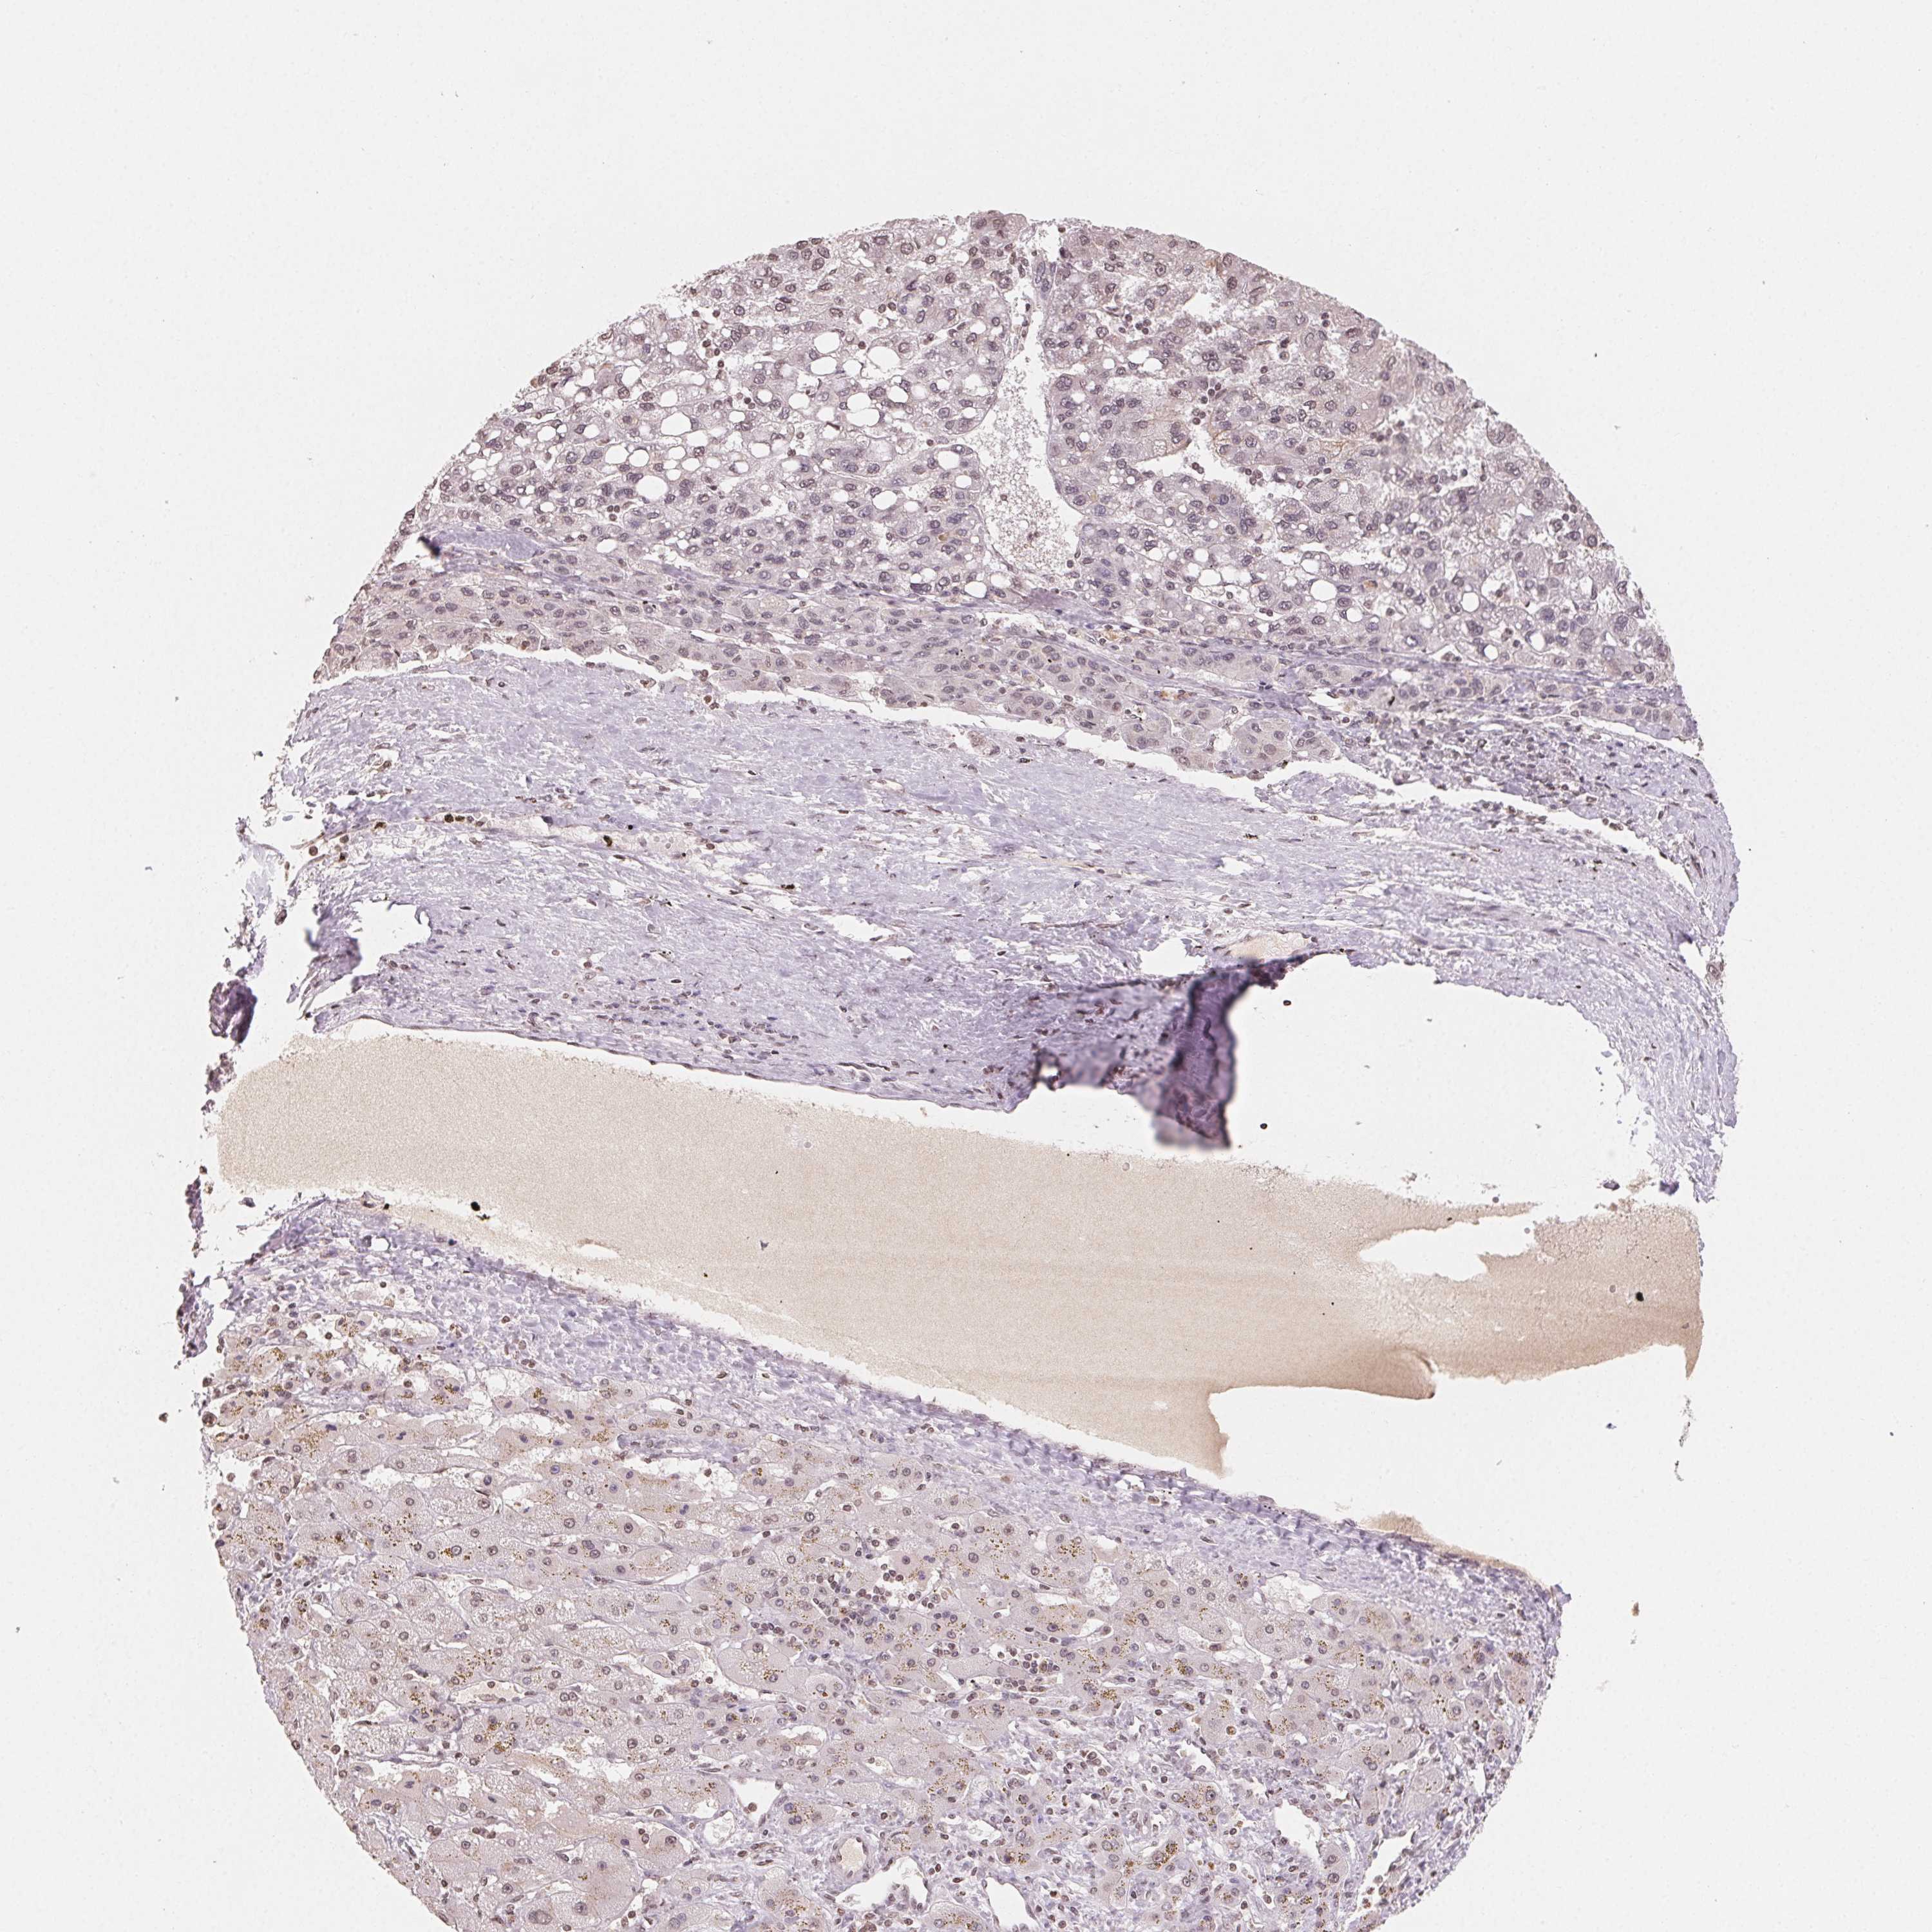

LIVER CANCER - Protein expressioni

A mouse-over function shows sample information and annotation data. Click on an image to view it in a full screen mode. Samples can be filtered based on level of antibody staining by selecting one or several of the following categories: high, medium, low and not detected. The assay and annotation is described here.

Note that samples used for immunohistochemistry by the Human Protein Atlas do not correspond to samples in the TCGA dataset.

Antibody stainingi

Antibody staining in the annotated cell types in the current human tissue is reported as not detected, low, medium, or high, based on conventional immunohistochemistry profiling in selected tissues. This score is based on the combination of the staining intensity and fraction of stained cells.

Each image is clickable and will lead to virtual microscopy that enables deeper exploration of all samples and also displays staining intensity scores, fraction scores and subcellular localization as well as patient and tissue information for each sample.

Antibody HPA049805

Staining

High

Medium

Low

Not detected

Intensity

Strong

Moderate

Weak

Negative

Quantity

>75%

75%-25%

<25%

None

Location

Nuclear

Cytoplasmic/membranous

Cytoplasmic/membranous,nuclear

Carcinoma, Hepatocellular, NOS

Cholangiocarcinoma